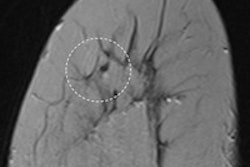

The modalities and procedures with a higher risk of a legal claim were mammography, breast ultrasound, total-body MR, total-body CT, and ob/gyn ultrasound. Lower-risk modalities and procedures were cardiac ultrasound, radiography of the extremities, and total-body radiography.